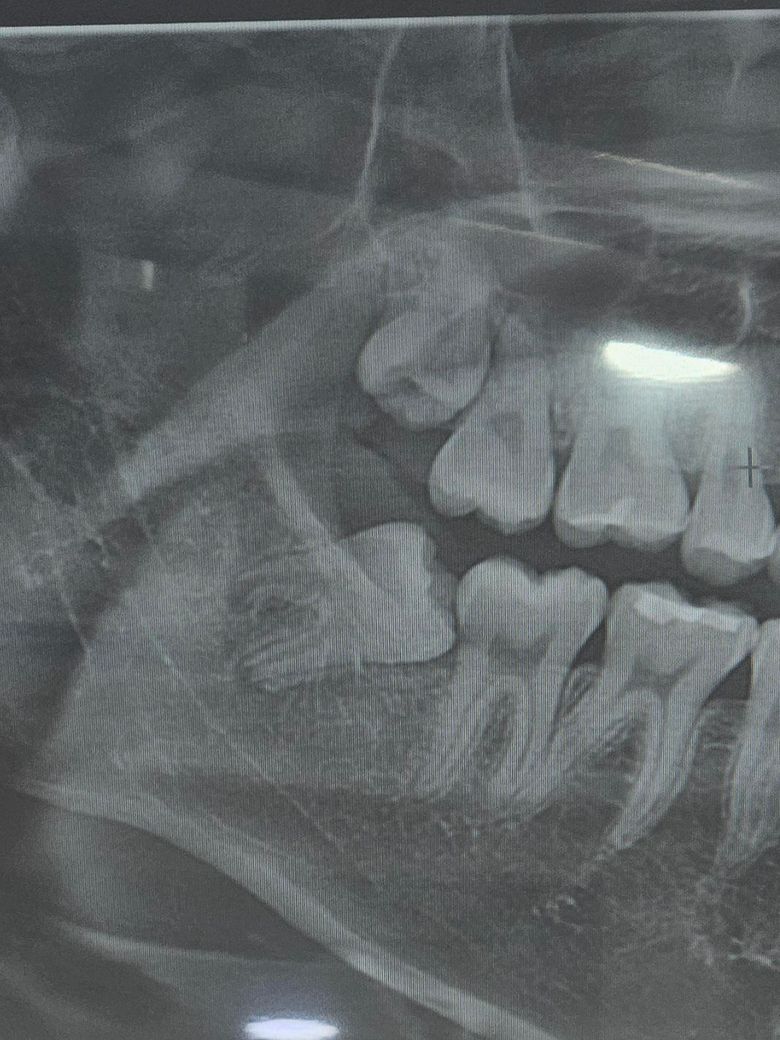

오른쪽 위,아래 사랑니 모두 존재하며 특히 아래 사랑니는 일부 맹출(잇몸 속에서 나옴)하여 앞쪽 큰 어금니 뒤쪽에 걸린(Locking) 상태로 보입니다.

이 경우 큰 어금니와 사랑니 사이 틈새가 양치질로 완벽하게 청소하기 어렵게 되고, 결과적으로 충치 및 잇몸질환에 취약해집니다.

네 위아래로 마지막 치아는 사랑니입니다 아래는 앞으로 문제를 일으킬 가능성이 많은 사랑니이므로 빼는 것을 권장드리고, 위에는 이미 충치가 약간 있는것 같습니다.